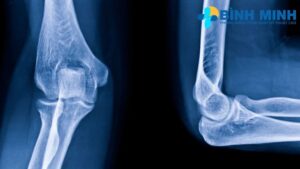

Phòng khám sử dụng máy X quang kỹ thuật số tiên tiến, đạt chuẩn quốc tế, cung cấp hình ảnh sắc nét và chi tiết. Công nghệ này giúp giảm thiểu lượng tia X, đảm bảo an toàn cho bệnh nhân, đồng thời hỗ trợ bác sĩ phát hiện chính xác các tổn thương xương khớp.

- Gãy xương: Xác định vị trí và mức độ gãy xương do chấn thương.

- Thoái hóa khớp: Phát hiện dấu hiệu mòn sụn, gai xương hoặc hẹp khe khớp, thường gặp ở khớp gối, cột sống, hoặc khớp háng.

- Viêm khớp: Nhận diện các dấu hiệu viêm khớp dạng thấp, viêm cột sống dính khớp, hoặc viêm khớp do gout.